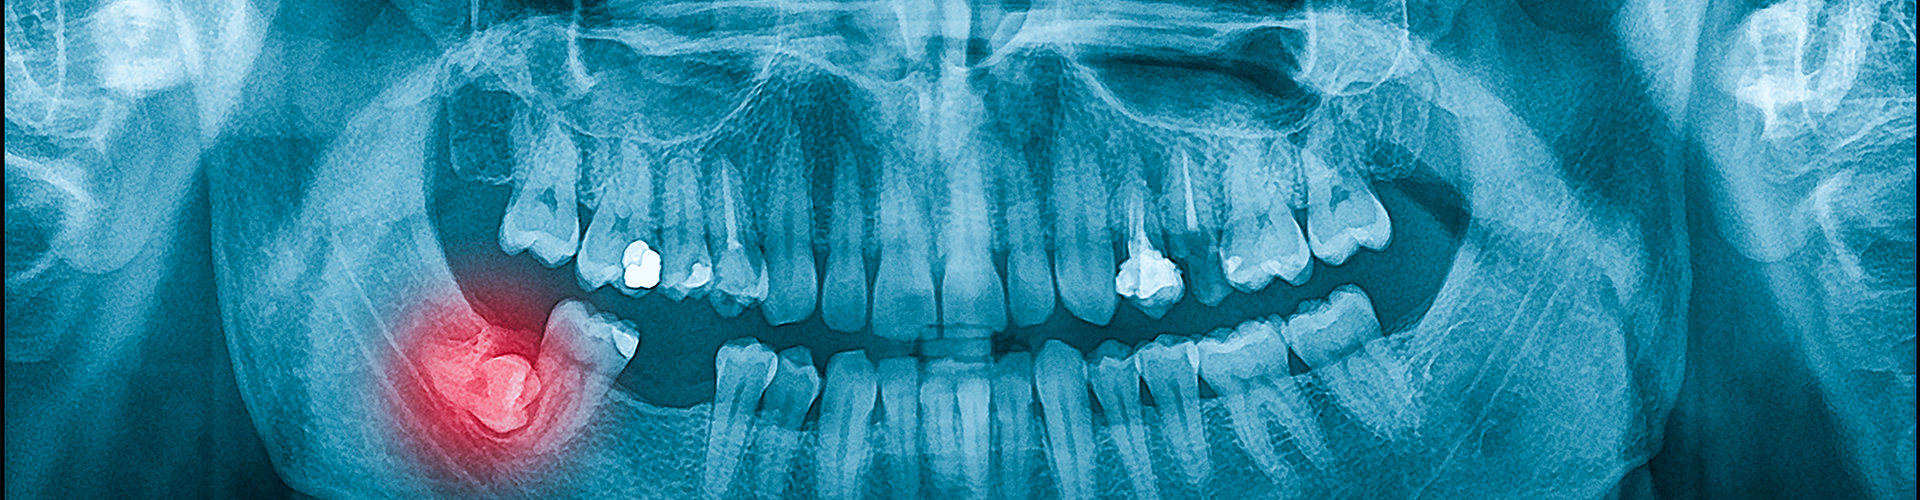

Recognizing these symptoms early on is vital for preventing further complications. Impacted wisdom teeth can lead to more severe dental problems if left untreated, such as cysts, tooth decay, gum disease, or damage to adjacent teeth. If you experience any of these symptoms, it’s important to consult your dentist promptly. They can assess your condition, often using X-rays, to determine the best course of action, which may include monitoring the teeth or recommending extraction to alleviate your symptoms and protect your overall oral health.

1. Initial Assessment and Diagnosis: The first step in treating impacted wisdom teeth is a thorough examination by your dentist. This usually includes a physical examination of your mouth and gums, as well as dental X-rays to assess the position and condition of the wisdom teeth. X-rays are crucial for determining the angle of the teeth, their proximity to adjacent teeth, and whether they are partially or fully impacted. This detailed imaging allows your dentist to evaluate the extent of the impaction and any potential issues, such as cysts, infections, or damage to neighboring teeth.